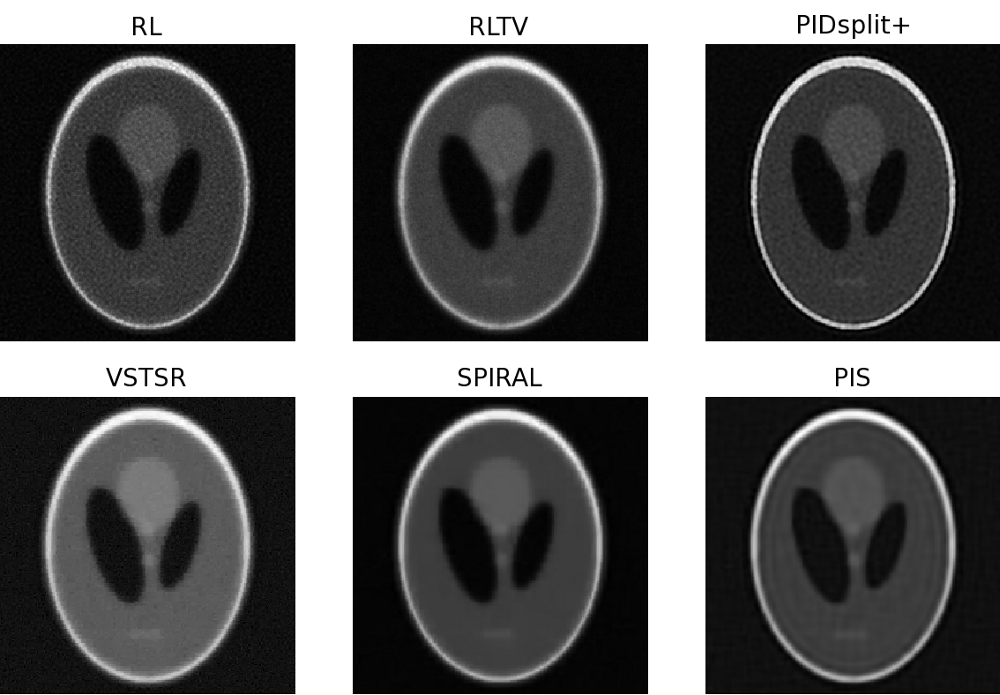

In this subsection, image reconstructions produced by the proposed and reference methods are tested using a microscopic image of glomerulus and the standard Shepp-Logan phantom, which are shown in Subplots A of Fig. 4 and Fig. 5, respectively. Similar to the case of sparse reconstruction, the images have been offset by a constant (background) value to give rise to different values of SNR. In particular, the value was adjusted to result in SNR equal to 32 (moderate noises) and 8 (strong noises). The original, blurred, and contaminated images of the glomerulus and Shepp-Logan phantom are summarized in Fig. 4 and Fig. 5 for all the tested values of and SNR.

For the case of glomerulus, the reconstructions obtained with the proposed and reference methods are summarized in Fig. 6 (for , SNR=32) and Fig.7 (for , SNR=8). Moreover, Fig. 8 and Fig. 9 depict the reconstructions of the Shepp-Logan phantom for the cases of , SNR=32 and , SNR=8, respectively. Analyzing these results, one can clearly see that, in all the above cases, the PIS algorithm yields reconstructions of superior quality (in terms of the resolution and contrast gain), as compared to the reference methods. This observation is further supported by the quantitative measures of Tables III and IV, which compare the estimation results in terms of the NMSE, SSIM index, and the number of iterations. As evidenced by the tables, the PIS method produces the lowest NMSE and the largest SSIM index among all the methods under comparison. As to the number of iterations required by PIS, one can see (with a reference to Table II) that the method has a computational complexity either comparable or lower than that of the reference methods.